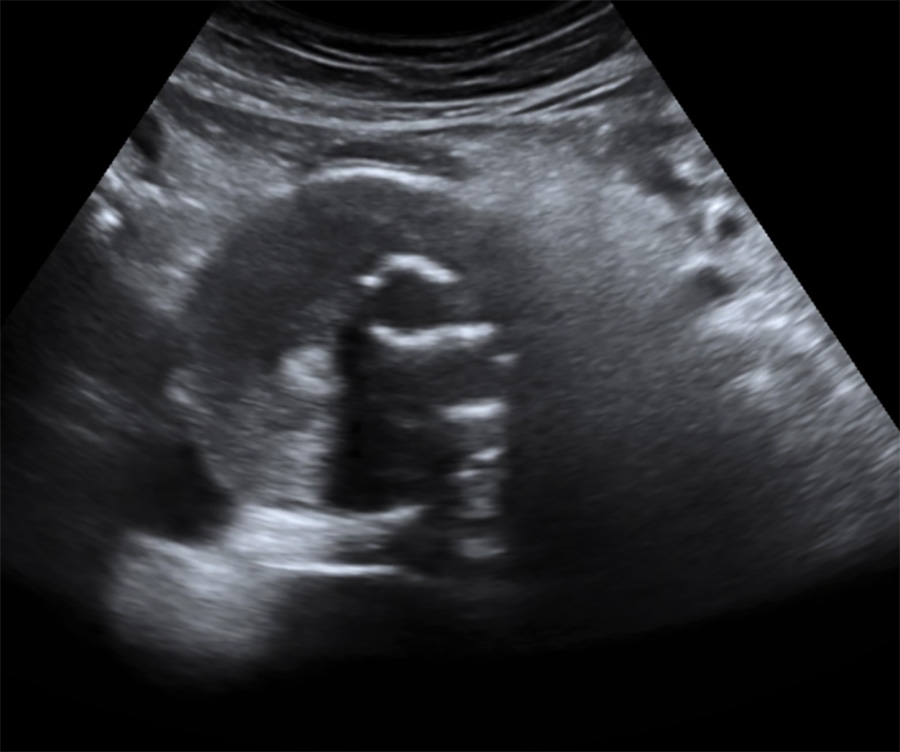

Aspect échographique en coupe axiale